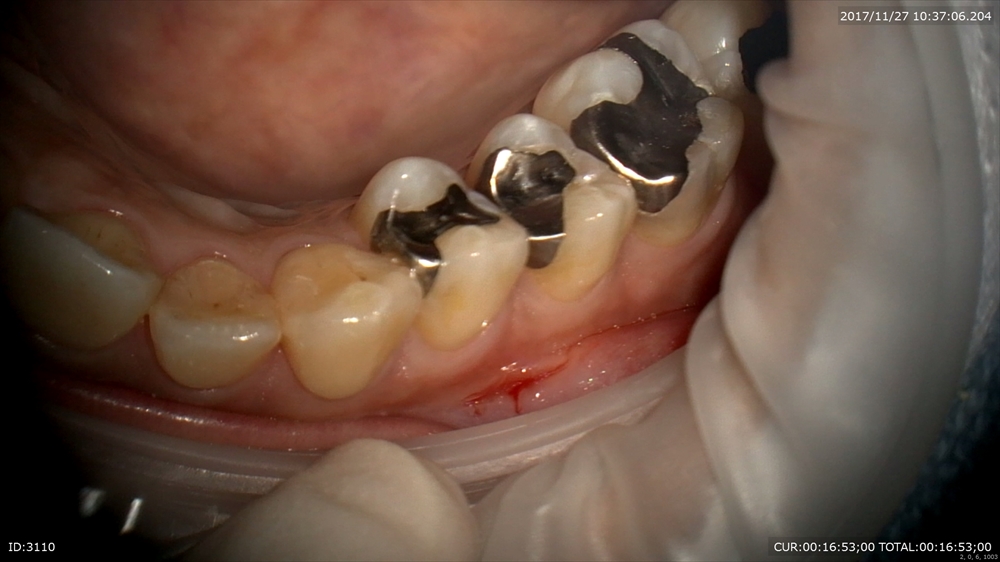

では証拠に本日の虫歯の治療の御紹介

一見健康に見える銀歯(一番手前)

歯科ドックで内部虫歯が発覚!こんなに大きく神経に近い。マイクロスコープで丁寧に。

神経を保護(MTAセメント)

修復。

術前(右)術後(左)金属を使わない治療は健康にも良いです。

患者さまにも喜んで頂けました。